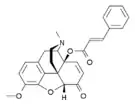

- 14-Cinnamoyloxycodeinone

14-Cinnamoyloxycodeinone 14-Cinnamoyloxycodeinone |